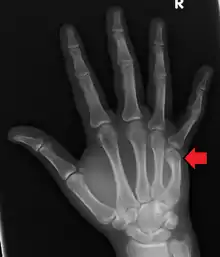

A healed fracture of the neck of the 5th metacarpal

Prognosis for these fractures is generally good, with total healing time not exceeding 12 weeks. The first two weeks will show significantly reduced overall swelling, with improvement in clenching ability showing up first. Ability to extend the fingers in all directions appears to improve more slowly. Hard casts are rarely required, and soft casts or splints can be removed for brief periods of time to allow for cleaning and drying the skin underneath the splint.[11] Pain from injury varies person to person as with most injuries. Depending on the individual a course of over the counter or narcotic pain medication will suffice. Muscle atrophy of 5 to 15 percent may be expected, with a rehabilitation period of approximately 4 months given adequate therapy. In the mildest of cases, full rehabilitation status can be achieved within 3 to 4 months.